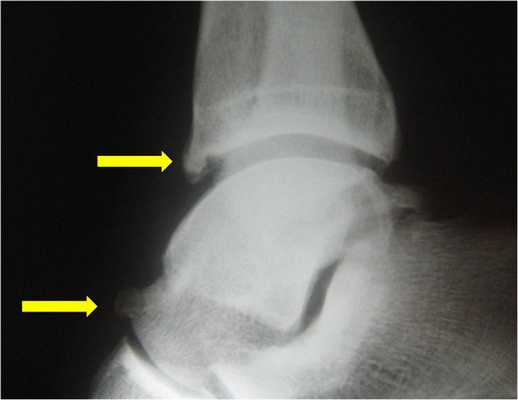

Визуализация переднего большеберцово-таранного импинджмента.Рекомендовано использовать прямую, боковую и косую проекцию при выполнении рентгенографии. На рентгенограммах определяются костные шипы в области дистального отдела большеберцовой кости или по тыльной поверхности таранной кости. Косые проекции позволяют определить остеофиты по передне-медиальной поверхности. КТ и МРТ позволяют более детально оценить степень разрастания остеофитов и их локализацию.

Рентгенография голеностопного сустава в боковой проекции, показывающая костные разрастания в области нижнего отдела большеберцовой кости и шейки таранной кости